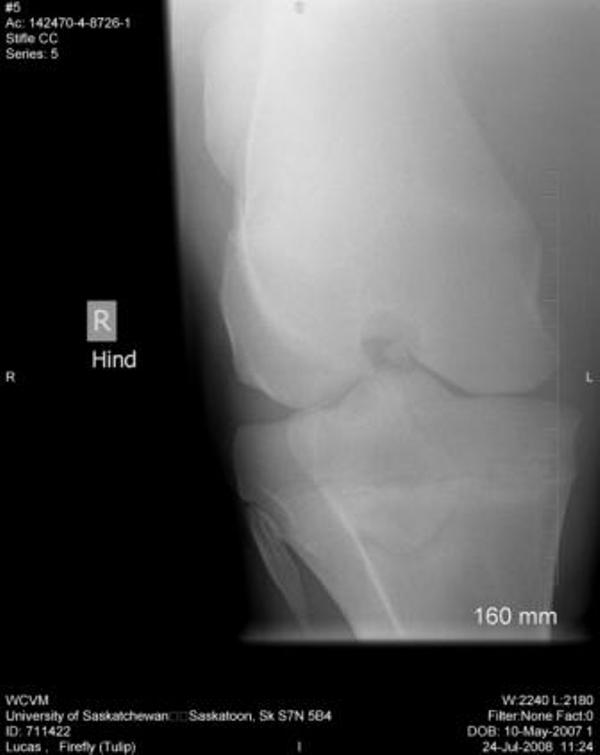

Right Stifle:

There is a fragmentation of the medial intercondylar eminence of the proximal right tibia. This is most likely an osteocchonDrOsis dissecans lesion. No other lesions are identified.

Thank you so much for your assistance, it is really appreciated!! I finally have the cd of the x-rays and will be posting them here. Again, thank you!! The first 2 are stifle pictures, the rest are of the hock.

Right stifle

Thanks Dr. O!! I really appreciate your taking a look at this. I do have Dr. Rantanen's report which is as follows:

Interpretation:

The most proximal portion of the right medial tibial spine was separated by an irregular fracture line. The fragment was still close to its anatomic position.

There was no soft tissue swelling or secondary joint disease present at this time.

Comment:

With the absence of clinical signs of lameness, normal flexion and no soft tissue swelling at this time, this fracture most likely occurred at a young age. It may be an incidental finding in this horse. Success in training would confirm that this fracture most likely occurred at a young age and may be tolerated without surgical intervention.